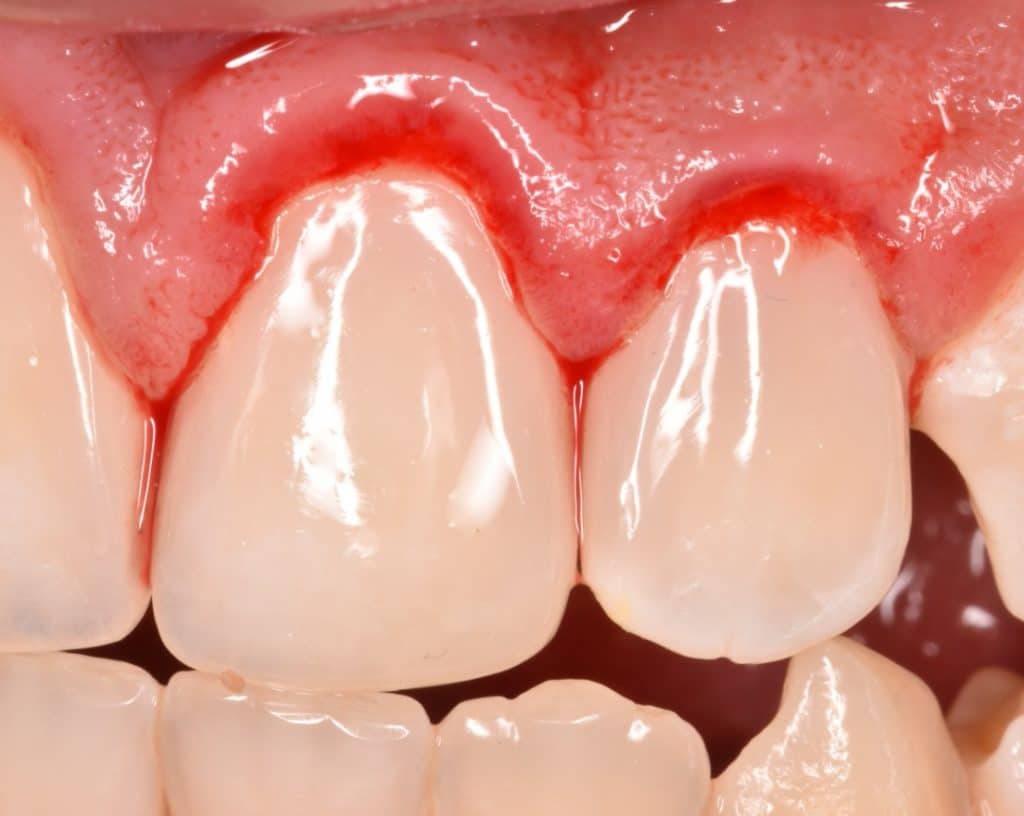

One month follow up

One month follow up, you can see the uniform color of the composite with the teeth 👍